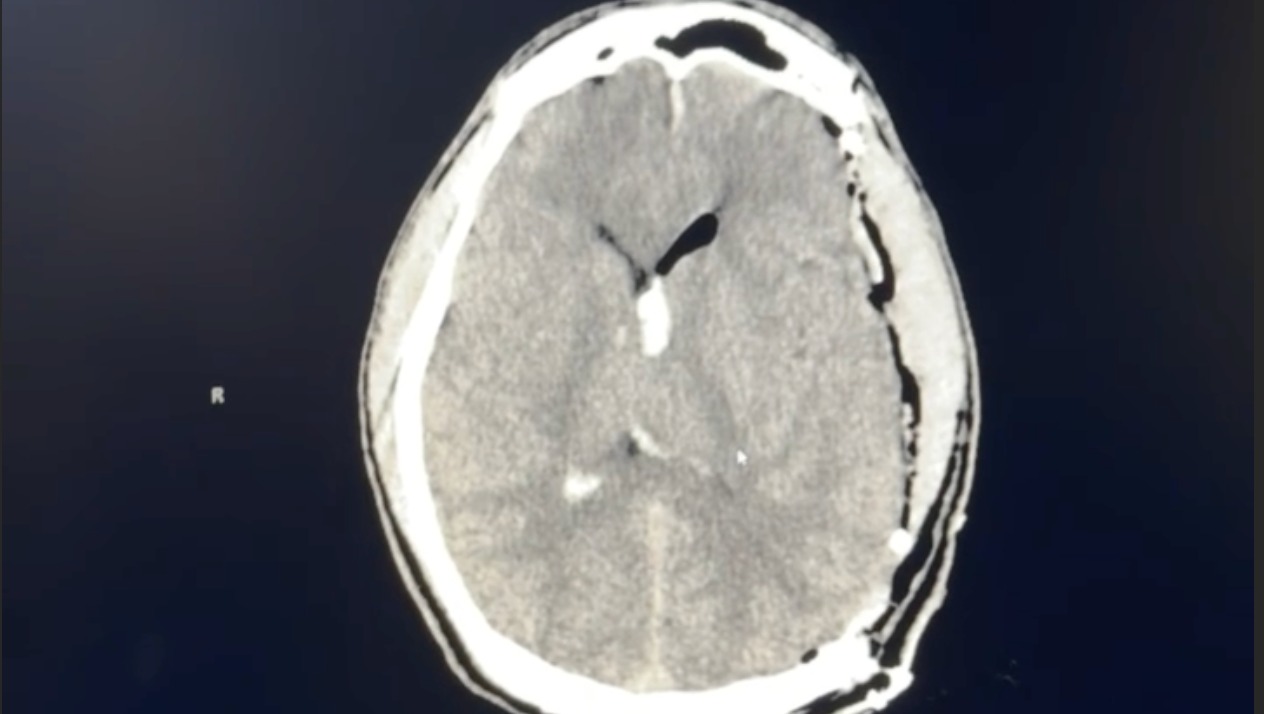

George suffered a ruptured brain AVM — an arteriovenous malformation. It's an abnormal tangle of blood vessels in the brain that he was born with. It had been there, silently, for 27 years without anyone’s knowledge. No symptoms. No warning signs. On March 26, it ruptured without any reason causing a hemorrhagic stroke, flooding the left side of his brain with blood.

The left side of the brain controls language, memory, and motor function.

During the emergency surgery, surgeons removed a section of George's skull to give his swelling brain room to survive. They evacuated as much of the hemorrhage as possible and placed a drain to relieve the dangerous pressure. The surgery lasted over 6 hours and saved his life.

But the AVM itself — the root cause — was intentionally left untreated. Removing it during the emergency would have risked further brain damage. That requires its own surgery, and George's brain has to heal first.

George is now in stable condition. Follow-up scans show significant improvement and his doctors are cautiously optimistic.